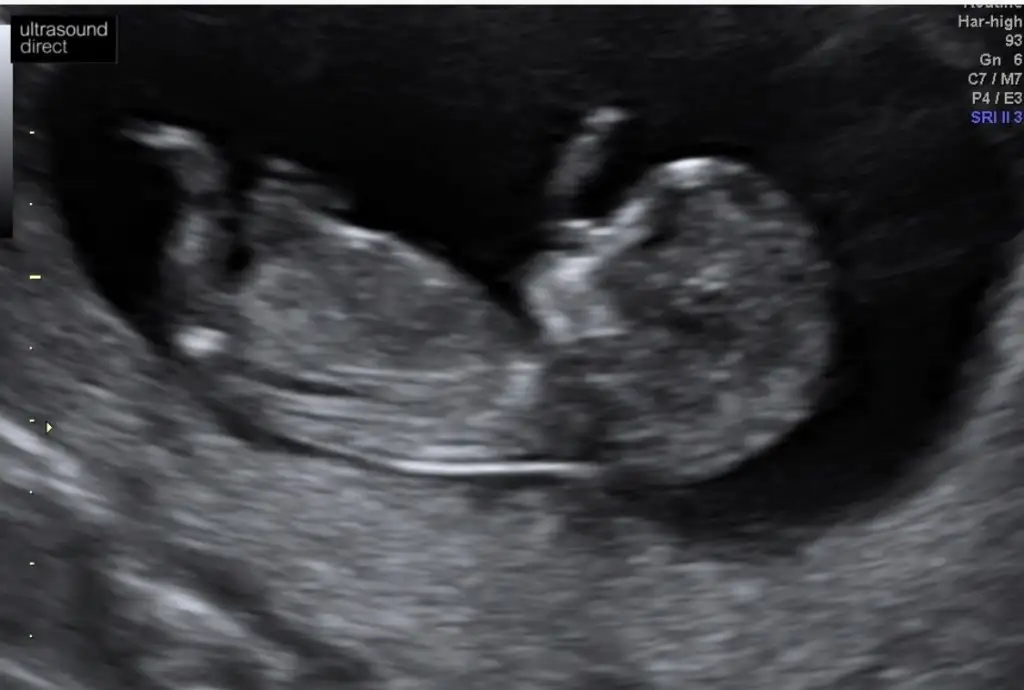

Anket Nub teorosi dogru tahminmi arkadaşlar

Nu teorisi dogrumu yanlışmı

• Tahminim dogrumu

OY: 357 76,6%

• Tahminim yanlışmı

OY: 109 23,4%

• Ankete Katılan

466

Valla dün 15+0 dı doktor hala yüzde yüz kız demedi 80 diyor:) ama zannetmiyorum değişeceğini daha öncede kız gibi demişti başka bi doktor